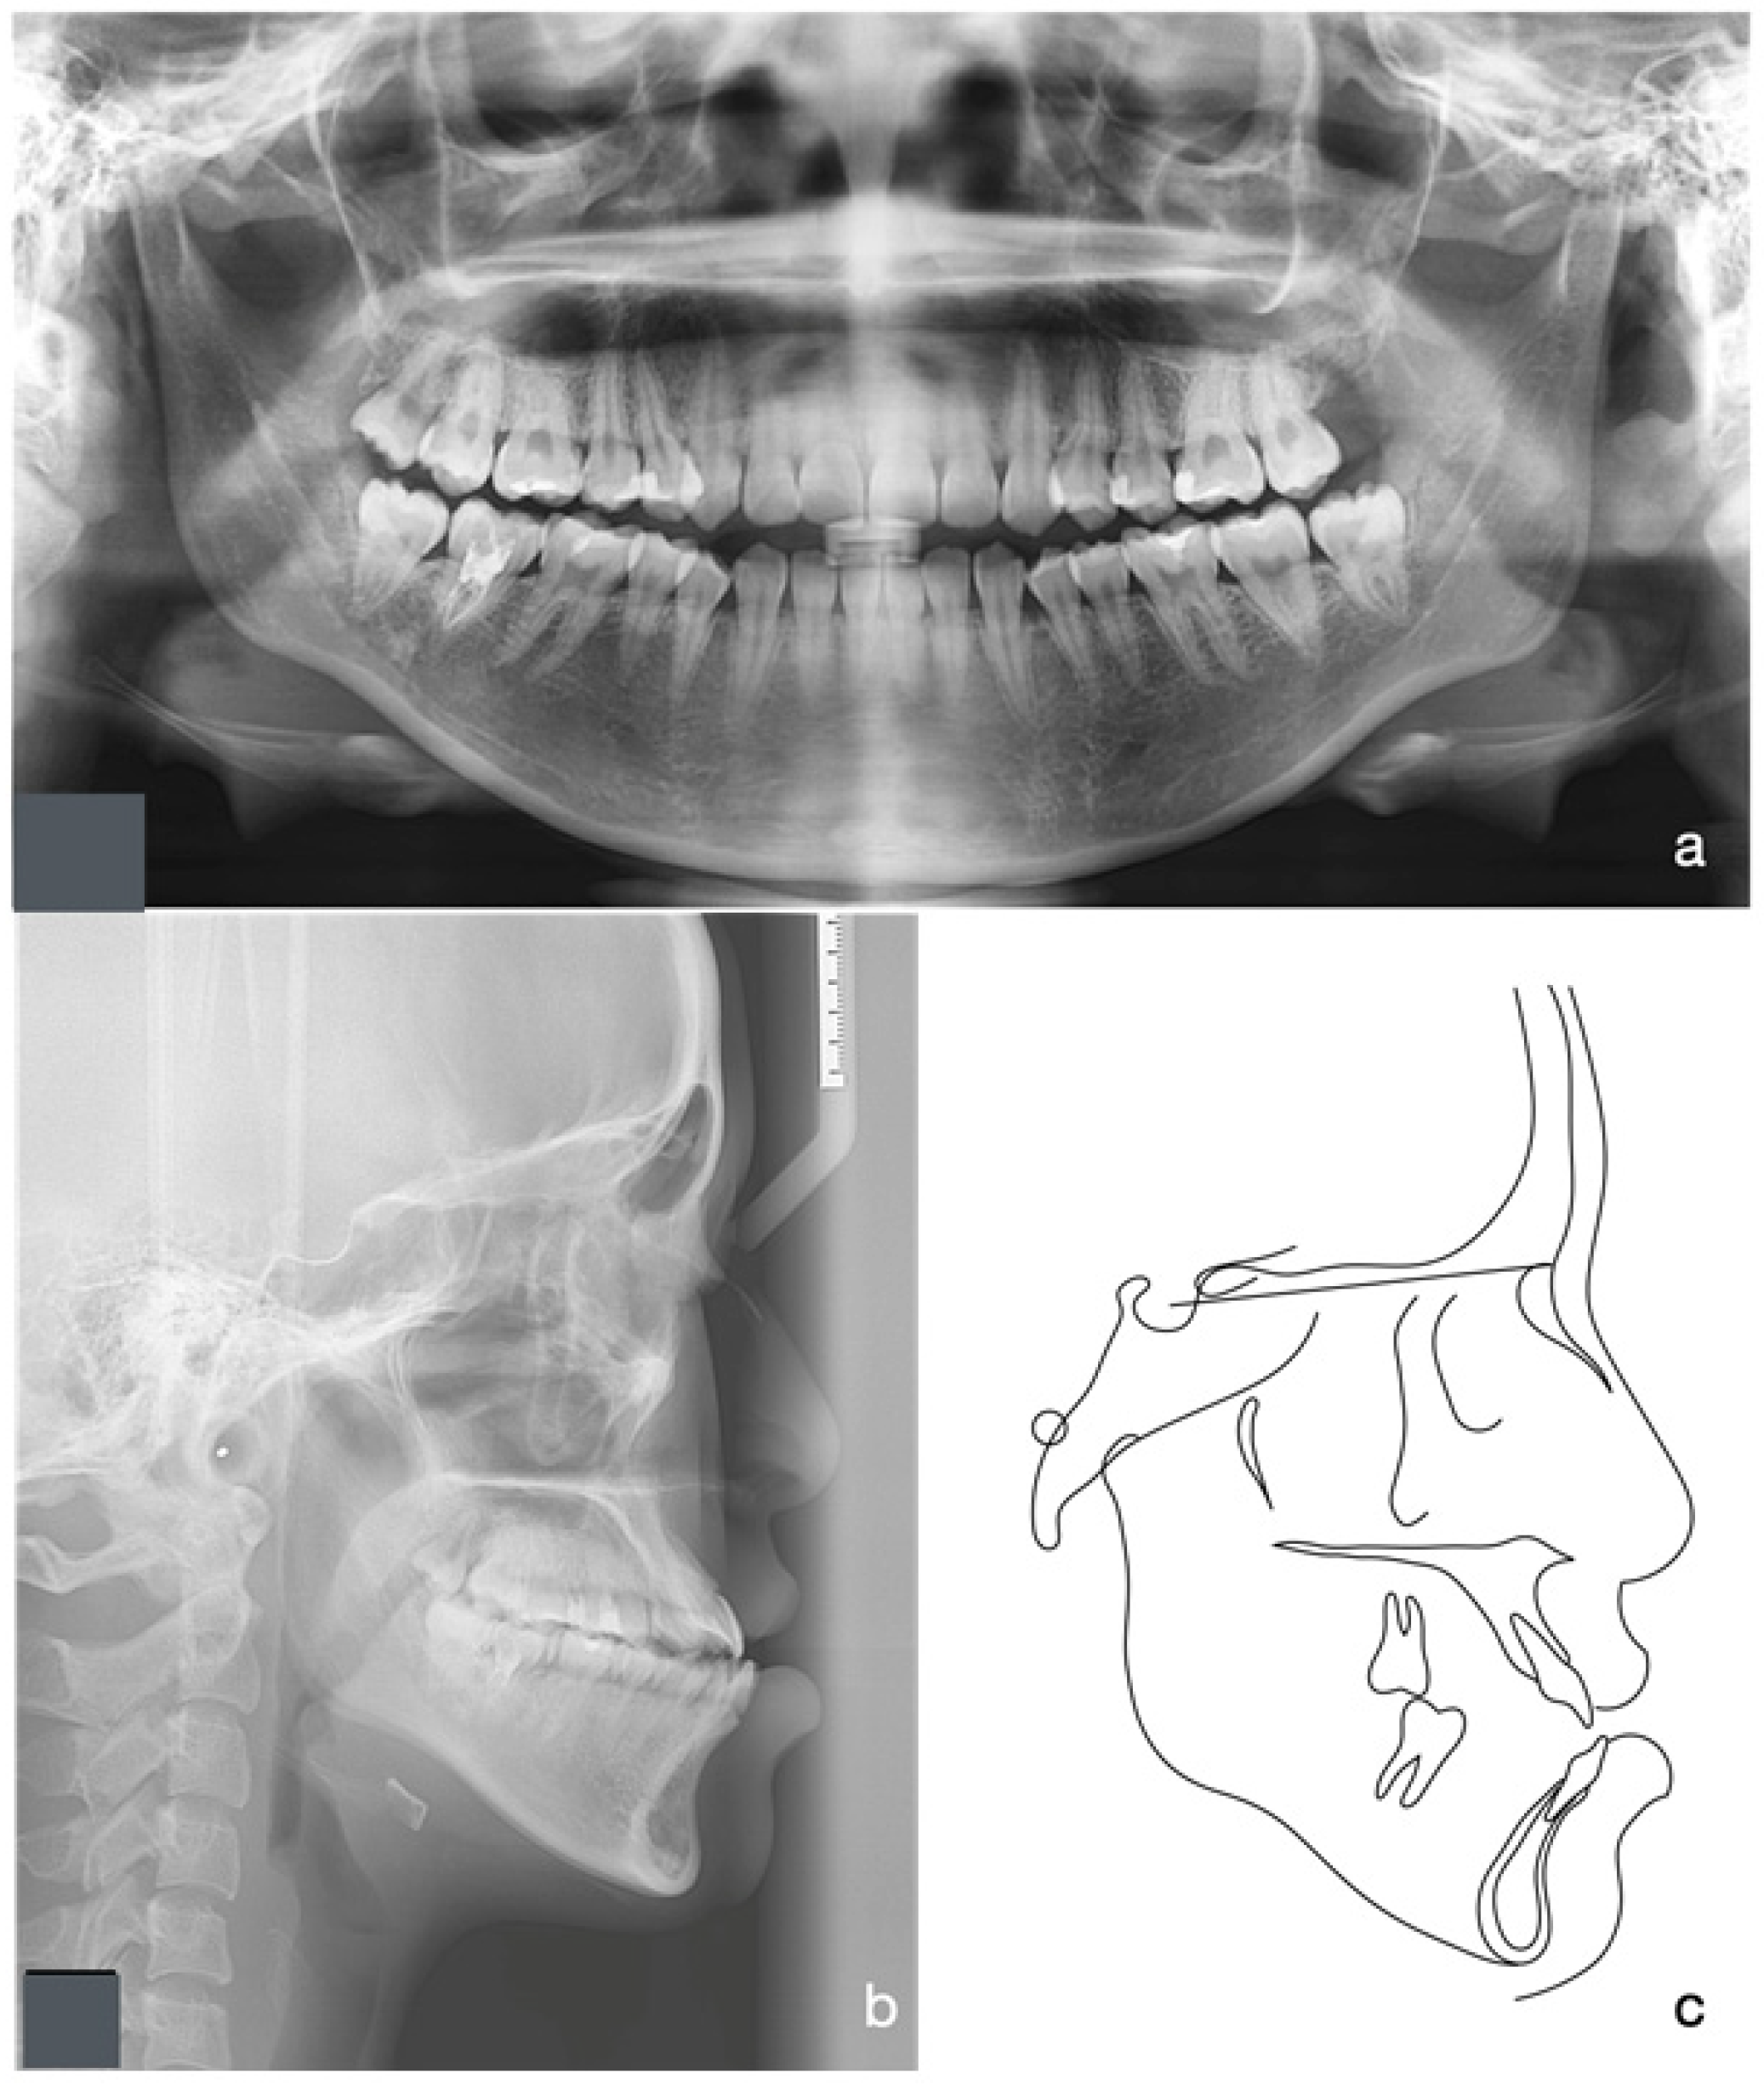

2.1. Diagnosis and Aetiology

2.4. Treatment Progress